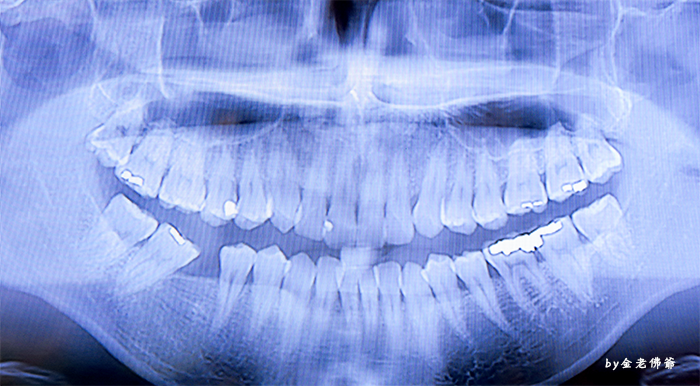

上次介紹的高水準數位X光室

聽說這器材來自日本

這次MIU喔爸親自在這邊使用了

來看看MIU喔爸拍出來的透明自拍

MIU喔爸牙齒真的不整齊

還缺了一個牙齒